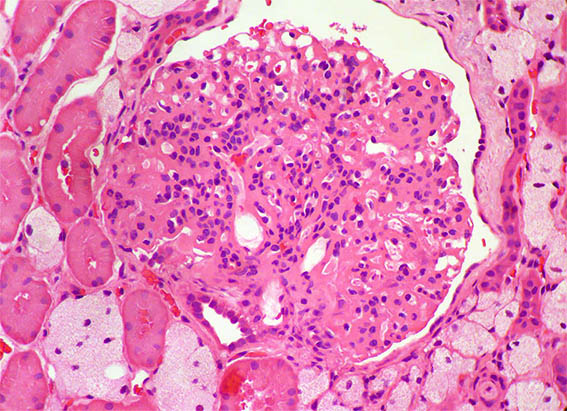

Figure 3.

H&E, X400.